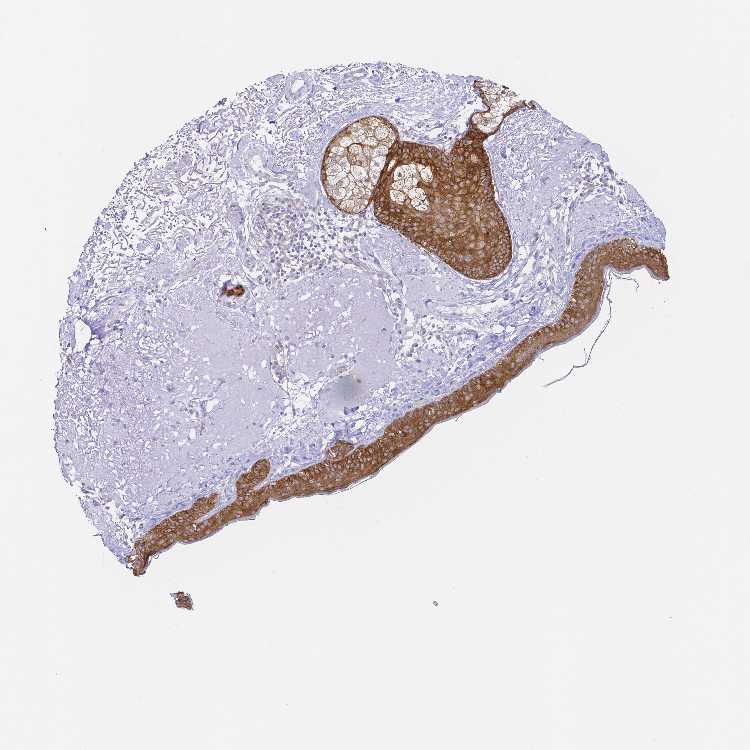

SKIN 2 - Antibody stainingi

Antibody staining in the annotated cell types in the current human tissue is reported as not detected, low, medium, or high, based on conventional immunohistochemistry profiling in selected tissues. This score is based on the combination of the staining intensity and fraction of stained cells.

Each image is clickable and will lead to virtual microscopy that enables deeper exploration of all samples and also displays staining intensity scores, fraction scores and subcellular localization as well as patient and tissue information for each sample.

Antibody HPA062937Antibody CAB012993

Cells in basal layer -High

Cells in corneal layer -Not detected

Cells in granular layer -Medium

Cells in spinous layer -Medium

Endothelial cells -Not detected

Epidermal cells High-

Extracellular matrix -Not detected

Fibrohistiocytic cells -Not detected

Langerhans cells -Medium

Lymphocytes -Not detected

Melanocytes -Not detected

Vascular mural cells -Not detected